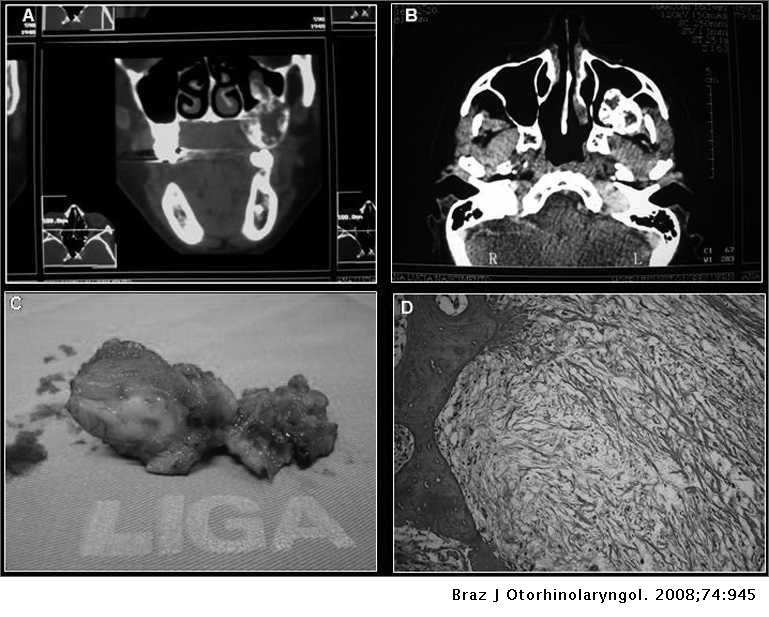

Odontogenic Myxoma Of The Maxilla Invading The Maxillary Sinus Brazilian Journal Of Otorhinolaryngology